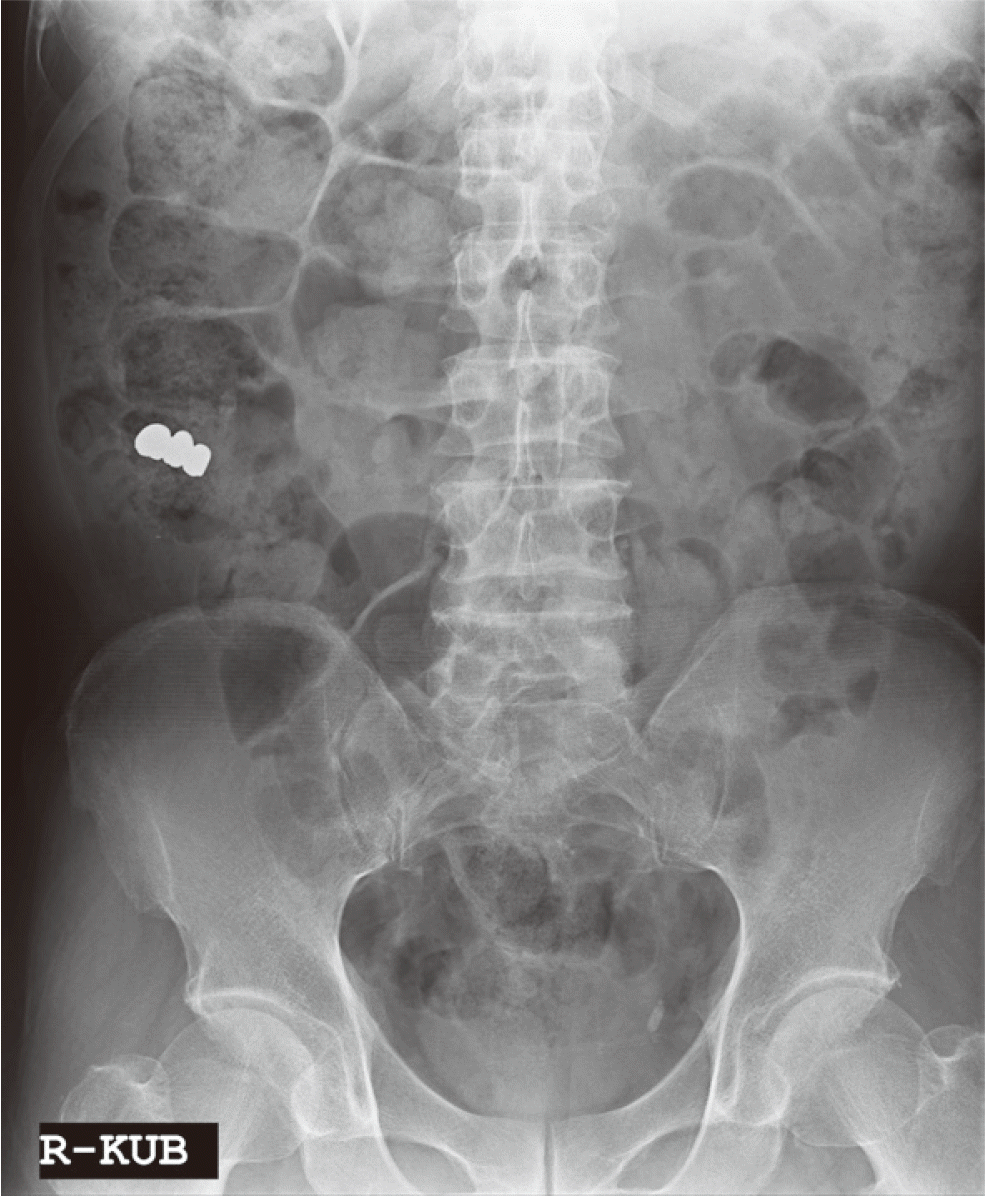

60세 남자 환자로 전체적인 치과치료를 위해 본원에 내원하였다. 환자는 의과적으로 기질성 정신장애를 진단을 받았으며, 거동이 불편하고 보행이 불가능하여 요양병원에서 입원 치료 중이었다. 정신건강의학과에서 환자의 정신장애에 대해 치료상태가 안정된 상태임을 확인한 후, 치과치료를 진행하였다. 파노라마 방사선 사진 및 구강검사에서 상악 우측 제1소구치와 제1대구치, 좌측 제제1, 2소구치, 하악 우측 제1대구치에 잔존 치근이 존재하였으며, 상악 우측 견치와 하악 좌측 견치 및 소구치에서 치아우식증이 관찰되었다(Fig. 1). 환자의 의과적 병력과 치료의 협조도, 구강위생 조절 능력 등을 고려했을 때, 가철성 보철물의 유지와 관리가 어렵다고 판단되어 고정성 보철물로 수복을 계획하였다. 예후가 불량한 상악 우측 견치, 제1소구치, 제1대구치와 좌측 제제1, 2소구치, 하악 좌측 견치, 제1소구치와 우측 1대구치를 발치 한 후, 치아 상실부위에 임플란트 식립을 하였고(Fig. 2), 골유착 기간을 거쳐 최종인상을 채득하였다. 제작한 임플란트 보철물을 장착하던 과정에서 치과의사는 하악 우측 제제1, 2소구치와 제1대구치로 이루어진 3본 지르코니아 보철물이 환자의 구강 내로 떨어뜨렸고, 떨어진 즉시 환자의 두부를 좌측으로 돌려 환자가 보철물을 삼키지 않도록 노력하였으나, 환자가 보철물을 삼키게 되었다. 환자가 보철물을 삼킨 이후 기침이나 구토 반사 등의 특이적 소견을 보이지 않았으며, 호흡상태는 양호하였다. 환자 보호자에게 보철물 장착과정에서 보철물을 구강 내로 떨어뜨렸고, 이후 삼킴이 발생하였음을 설명하였다. 그리고 삼켜진 보철물의 위치 확인을 위하여 인근 내과로 전원 의뢰를 시행하였다. 전원 의뢰된 당일, 내과에서 복부 방사선 사진을 촬영하였고, 판독 결과 보철물이 위장에 위치를 하고 있음을 확인하였다. 24시간 이후 배출될 것으로 예상되어 48시간 후 재촬영이 필요할 것이라는 회신서를 확인하였다(Fig. 3). 2일 후 환자를 내원하도록 하여 추가로 복부 방사선 사진을 촬영하였다. 방사선 사진에서 위장관 내에서 보철물 확인되었다. 환자의 거동이 불편하여 위장관 운동이 저하되어 있는 상태이기 때문에 배출이 지연될 수 있다는 의과적 소견을 회신 받았다(Fig. 4). 8일 후 환자의 복부 방사선 사진을 촬영하였으며, 보철물이 위장관에서 완전히 배출되어 체 내에 있지 않음을 확인하였다(Fig. 5). 이 후 하악 우측 제1, 2소구치와 제1대구치에 새로운 보철물을 제작하여 최종 합착(Rely-X, 3M ESPE, St Paul, USA)을 시행하였다(Fig. 6).